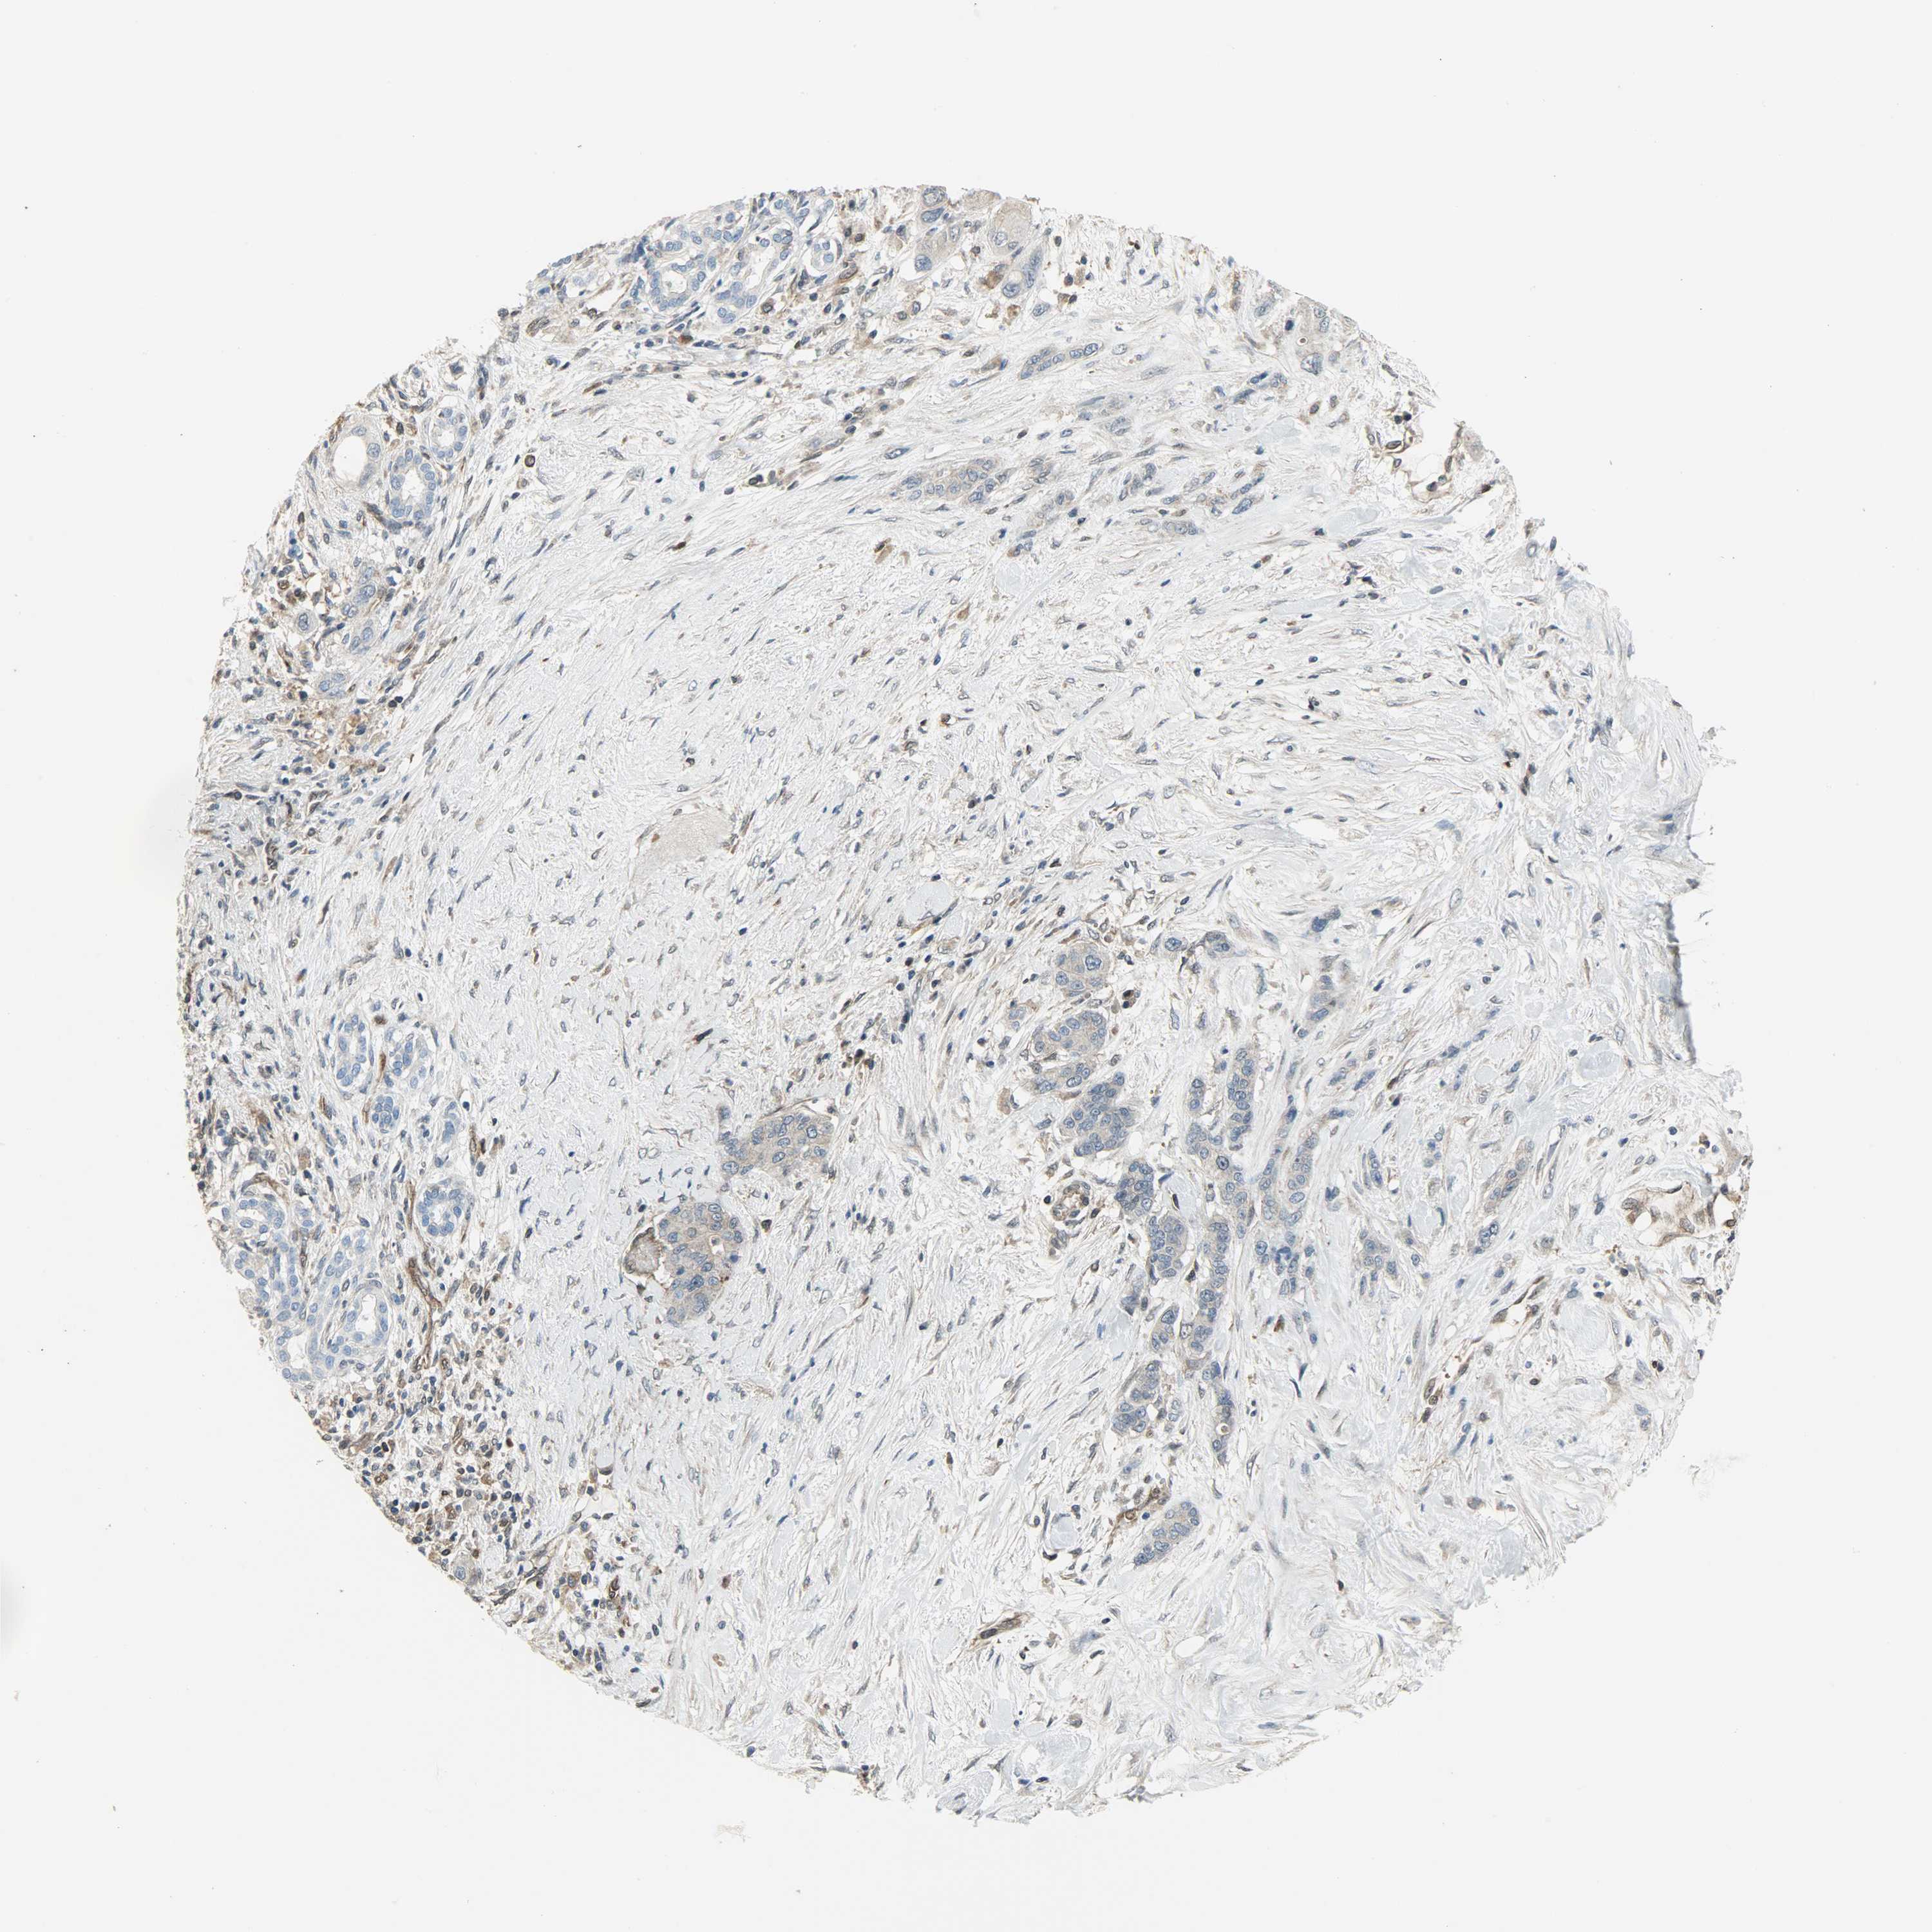

PANCREATIC CANCER - Protein expressioni

A mouse-over function shows sample information and annotation data. Click on an image to view it in a full screen mode. Samples can be filtered based on level of antibody staining by selecting one or several of the following categories: high, medium, low and not detected. The assay and annotation is described here.

Note that samples used for immunohistochemistry by the Human Protein Atlas do not correspond to samples in the TCGA dataset.

Antibody stainingi

Antibody staining in the annotated cell types in the current human tissue is reported as not detected, low, medium, or high, based on conventional immunohistochemistry profiling in selected tissues. This score is based on the combination of the staining intensity and fraction of stained cells.

Each image is clickable and will lead to virtual microscopy that enables deeper exploration of all samples and also displays staining intensity scores, fraction scores and subcellular localization as well as patient and tissue information for each sample.

Antibody HPA019007

Antibody CAB004641

Staining

High

Medium

Low

Not detected

Intensity

Strong

Moderate

Weak

Negative

Quantity

>75%

75%-25%

<25%

None

Location

Nuclear

Cytoplasmic/membranous

Cytoplasmic/membranous,nuclear

Adenocarcinoma, NOS

Adenocarcinoma, metastatic, NOS